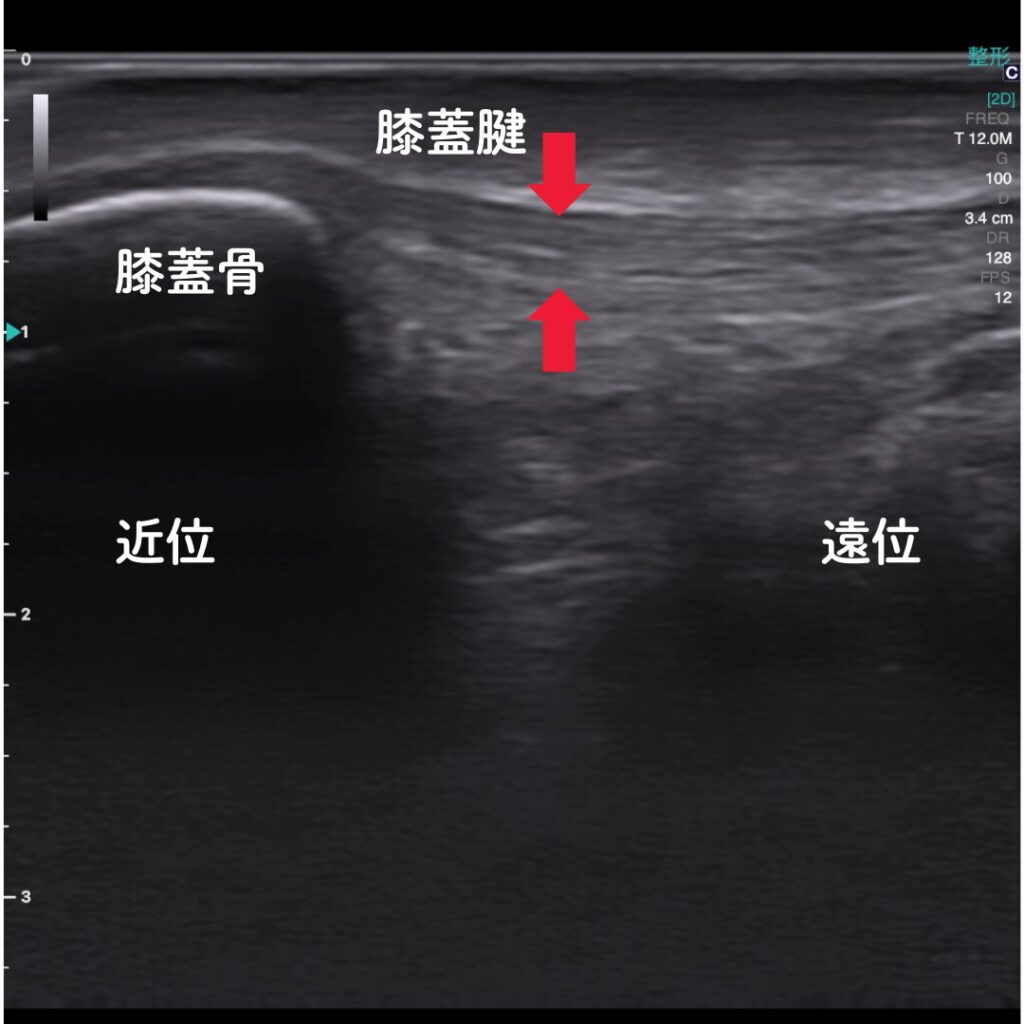

🔶エコー(超音波観察装置)で原因を“見える化”

エコー観察により、膝蓋腱の炎症や損傷の程度をリアルタイムで確認できます。

レントゲンでは写らない腱や軟部組織の状態を可視化し、痛みの原因を正確に特定します。

また腱付着部の骨異常も観察可能。